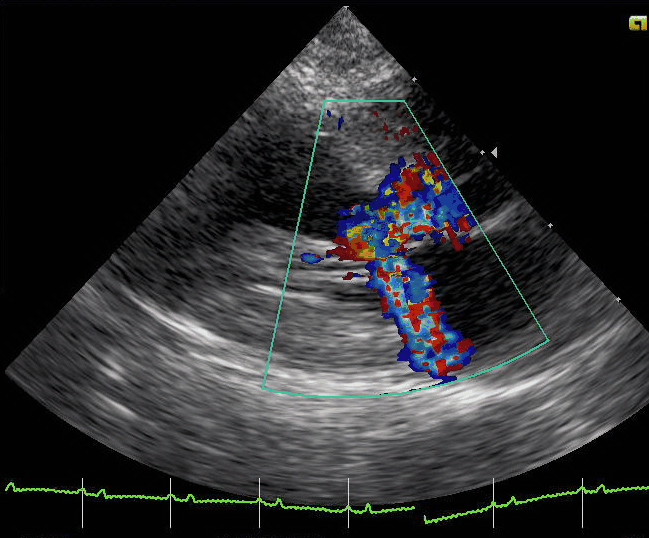

Video courtesy Minneapolis Heart Institute Foundation